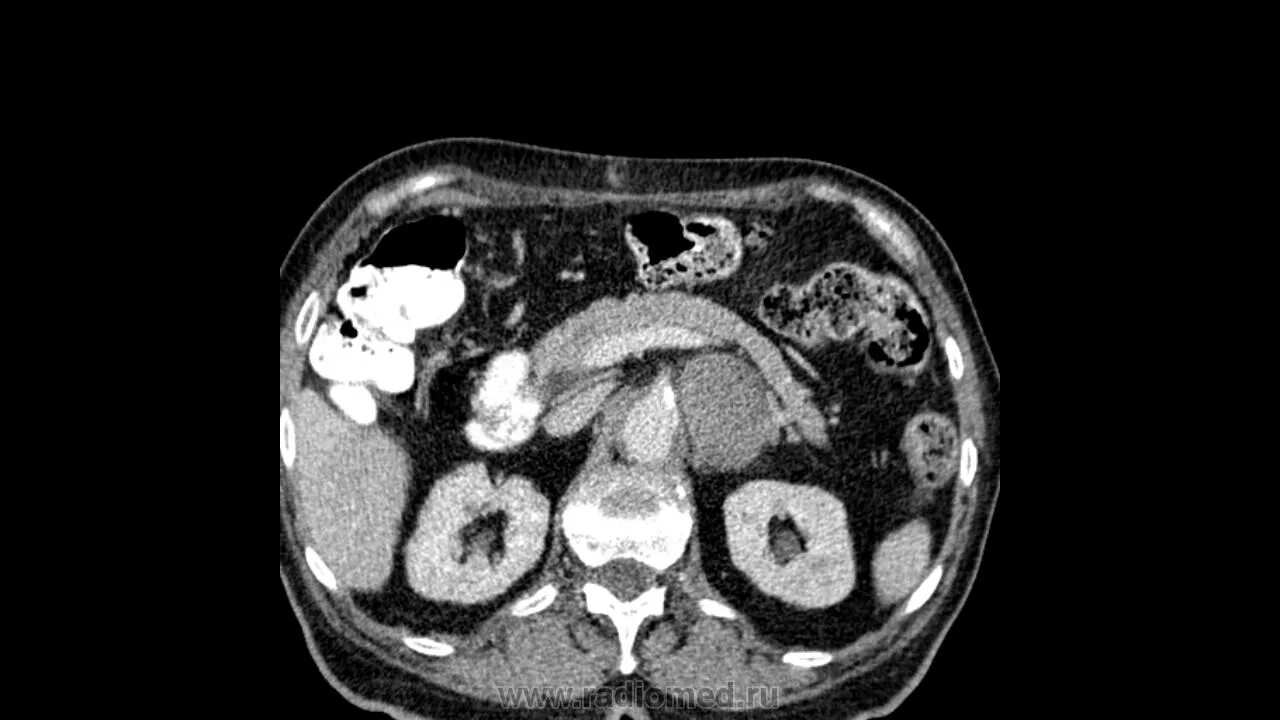

Забрюшинная онкология